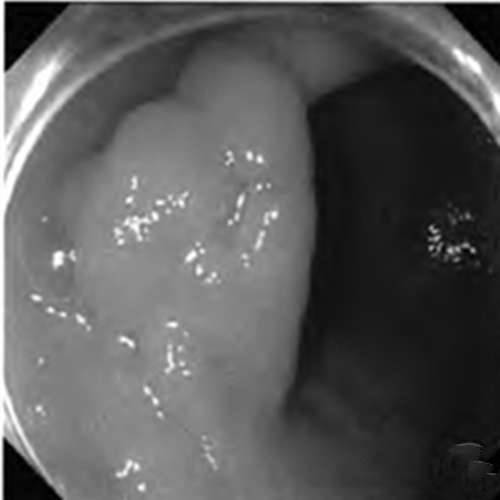

慢性胃炎圖片

慢性胃炎

慢性胃炎的

成人慢性胃炎

中型淺表萎縮慢性胃炎

萎縮淺表性慢性胃炎

萎縮性的慢性胃炎

萎縮性慢性胃炎

萎縮慢性胃炎

萎縮出血性慢性胃炎

輕型淺錶慢性胃炎

輕型淺表型慢性胃炎

縮的慢性胃炎

淺表型慢性胃炎怕

淺表型慢性胃炎

淺表型慢性胃炎萎縮

淺表型糜爛出血慢性胃炎

淺表型糜爛慢性胃炎

輕型慢性胃炎

淺表型慢性胃炎發發

淺表型慢性胃炎好